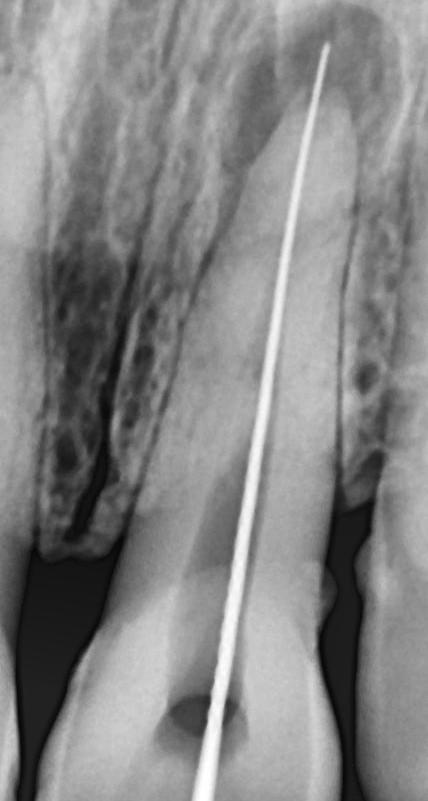

Opacity in root canal space

Was difficult but managed to negotiate. 18 june cropped